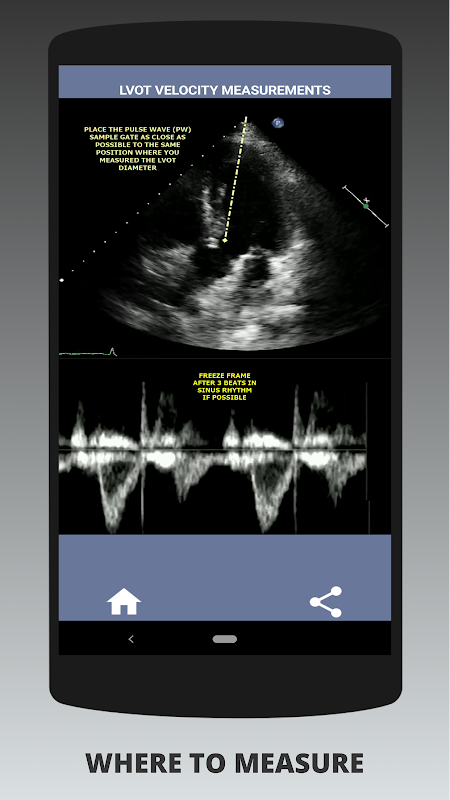

मेरी राय में, यदि एक साक्षात्कारकर्ता इस कौशल को दृढ़ता से प्रदर्शित कर सकता है तो उस व्यक्ति को अन्य आवेदकों पर एक बड़ा फायदा होता है जो इस क्षेत्र में कमजोर हैं (यह सिर्फ तार्किक है क्योंकि आमतौर पर बहुत सारे महाधमनी स्टेनोसिस के मामले होते हैं)। यदि आप कार्डियक सोनोग्राफर पद के लिए आवेदन कर रहे हैं, किसी ऐसे व्यक्ति को जिसे अपने कौशल को ताज़ा करने की आवश्यकता है, या एक इको छात्र है, तो इस ऐप को वर्तमान में अभ्यास करने वाले कार्डियक सोनोग्राफर द्वारा आपके लिए डिज़ाइन किया गया था। सरल और संक्षिप्त, कई दृष्टांत वीडियो के साथ सही बिंदु पर इंगित करता है कि वास्तव में कहां मापना है (जैसे एलवीओटी व्यास) और प्रकाशित एएसई/आईसीएईएल दिशानिर्देशों के अनुसार कैसे मापना है।